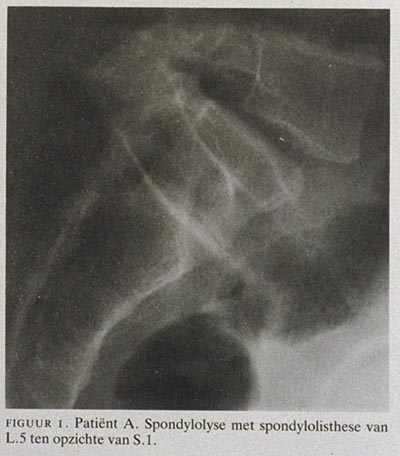

Bij onderzoek wordt alleen een dubieus niveauverschil tussen de processi spinosi van L.5 en S.1 gevonden. Röntgenonderzoek van de lumbale wervelkolom laat het beeld zien van een spondylolyse van de boog van L.5 met een anteropositie van L.5 ten opzichte van S.1 (figuur 1). Uitleg geven aan patiënt over de aard van de aandoening volstaat als behandeling. De jonge man wordt wel afgekeurd voor militaire dienst.